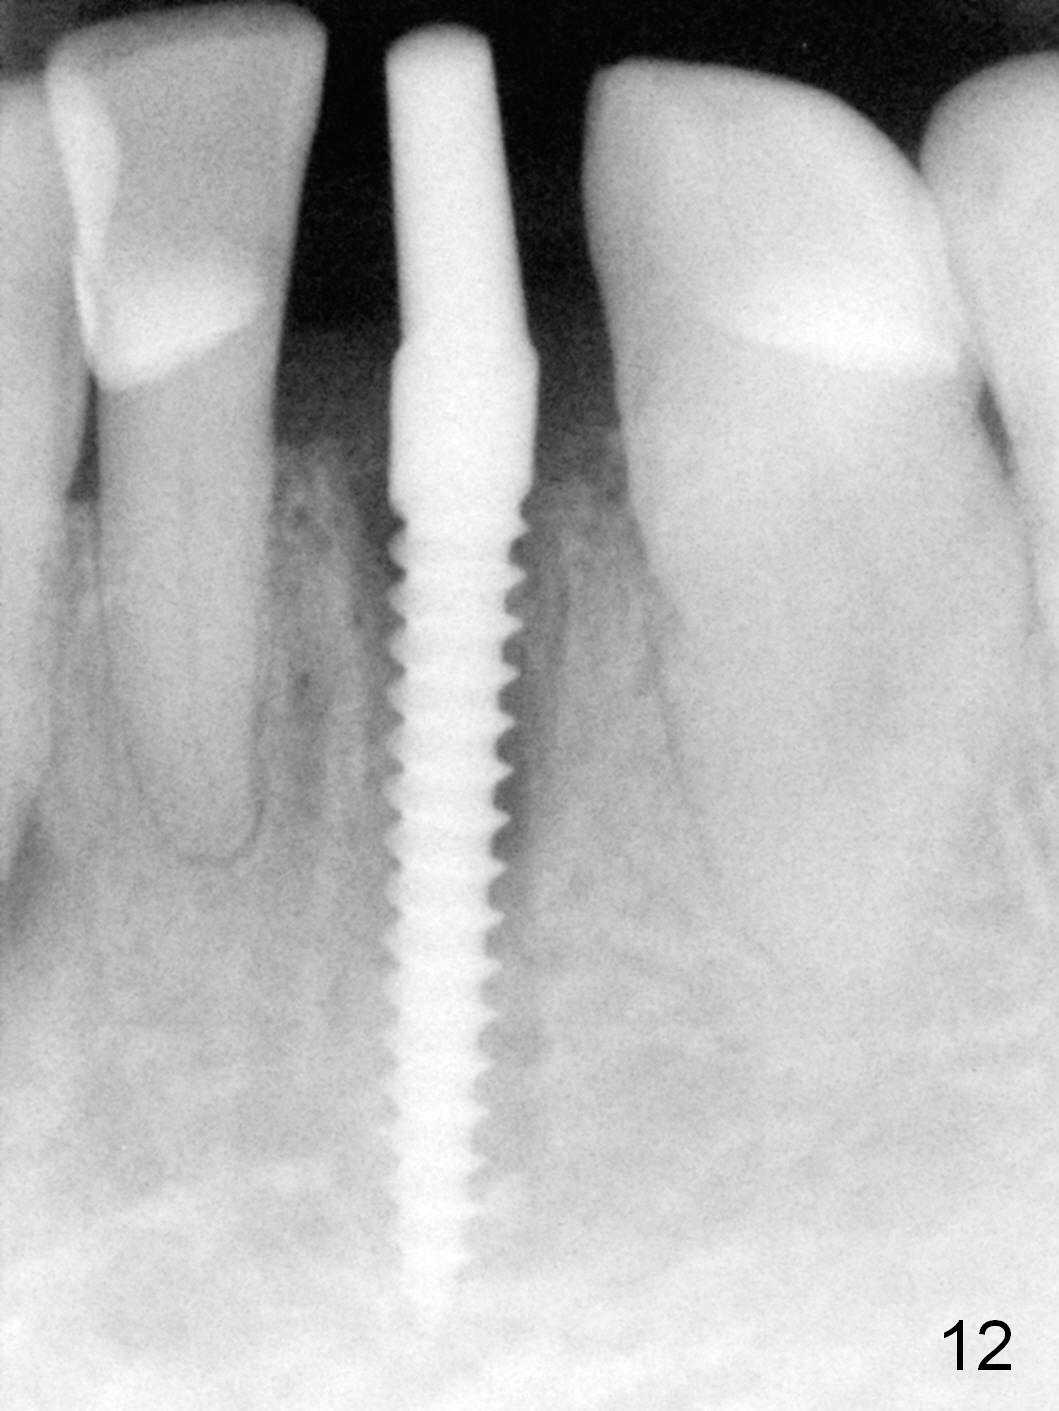

A 74-year-old man has several missing teeth (Fig.1). His 1st goal is to replace the lower left lateral incisor (Fig.2). The residual root has an apical lesion (Fig.3 *). To describe intraop findings, a CT image of a different patient is used (Fig.4 coronal section; B: buccal; L: lingual). After extraction, the buccal plate is found to be thin and low (Fig.5 arrowheads). A 1.5 mm pilot drill (Fig.6 red line) is used to initiate osteotomy in the lingual plate of the socket. Once the drill penetrates the lingual plate, the trajectory changes and the depth is 17 mm from the gingival margin (Fig.7). A PA is taken (Fig.8); it appears that the osteotomy can be extended more apically. When the pilot drill extends to 20 mm, there is sudden empty feeling. The lingual plate has perforated (Fig.9). A new osteotomy is established buccally (Fig.10 pink). To avoid buccal plate perforation, especially in the buccal undercut area (>), the coronal end of the drill has to be tilted buccally (<--). An angled abutment (3x20 mm, 15°) is placed (Fig.11,12). The abutment is modified (Fig.13,14) to accommodate an immediate provisional (Fig.15,16 P). Perio dressing is to be applied to prevent the bone graft from getting dislodged buccally (Fig.15). The dressing is in place 7 days postop (Fig.17).